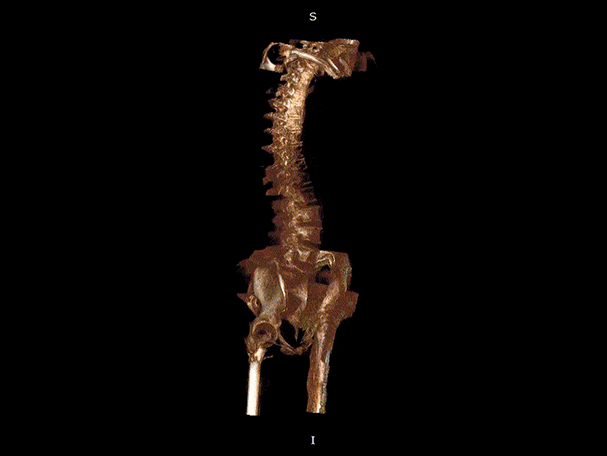

髖關節

頸椎

腰椎

VR體繪制重建